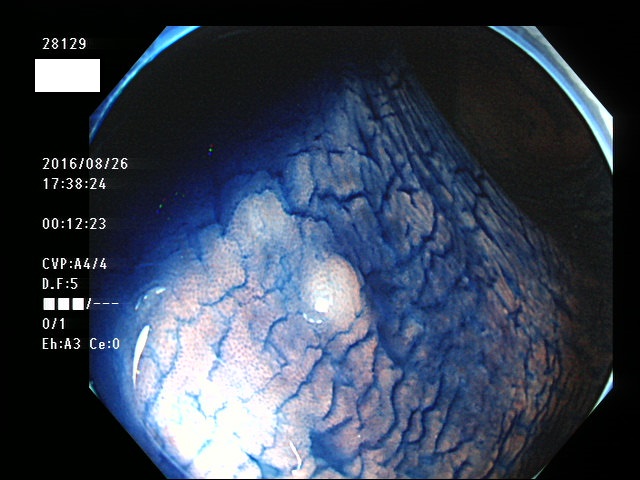

微小カルチノイドの診断

直腸の微小カルチノイドの診断は最も難しい問題です

微小とはいえ、カルチノイドは悪性であり、肛門に近い場所に好発するために、見落とすと数年後には「人工肛門」になる危険があります

進行したカルチノイドの診断は容易なのですが、カルチノイドは「粘膜下腫瘍」と言いまして、は表面が正常粘膜で被われているために微小ですと「単なる過形成結節」「単なる炎症性の隆起」と区別がつかないのです

下記の写真は全て、当院で診断された微小カルチノイド(悪性)ですが、いかに診断が困難かお分かりいただけるでしょう。このような微小病変でさえも見落とせば人工肛門の危険が潜んでいる訳です。